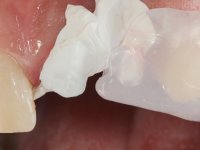

Foi feito o tratamento endodôntico dos dentes 2.1 e 2.2.de imediato, a sintomatologia que o paciente manifestava a isso impunha. Na mesma consulta foi realizada uma extensa gengivetomia com o bisturi elétrico, no sentido de expor os limites cervicais da fratura. Foram colocadas resinas compostas nos remanescentes radiculares com a intenção de reformular a emergência dos tecidos moles. Realizei a impressão dos remanescentes radiculares para confeção em laboratório de uma ponte provisória. A ponte provisória de 2 elementos, apresentava um formato que visava no futuro acomodar o coto dos espigões falsos cotos que iria ser cimentados nos remanescentes radiculares. Apresentava um reforço metálico palatino e dois apoios para os dentes adjacentes, um mesial e outro distal. Os remanescentes radiculares foram preparados para a confeção de dois espigões falso coto fundidos. As linhas de acabamento cervical foram definidas e os canais radiculares desobturados e preparados. A impressão foi realizada com a utilização de tutores de plástico com a técnica de dupla mistura. O afastamento gengival foi feito utilizando pasta de caolino. A ponte provisória foi rebasada em boca com acrílico auto polimerizavel, cimentada provisoriamente sobre as raízes e os apoios colados aos dentes adjacentes. No laboratório foram confecionados os E.F.C. fundidos, tendo o cuidado de preservar espaço para a definição no re preparo dentário da linha de acabamento cervical. Removida a ponte provisória foi feita a cimentação dos E.F.C. fundidos com cimento de ionómero de vidro reforçado com resina. A ponte provisória teve que ser retocada para permitir a acomodação dos cotos e simultaneamente foi readaptada à redefinida linha de acabamento cervical. Durante 2 meses a ponte provisória acompanhou a estabilização periodontal das raízes traumatizadas e simultaneamente conseguiu a maturação da arquitetura gengival.